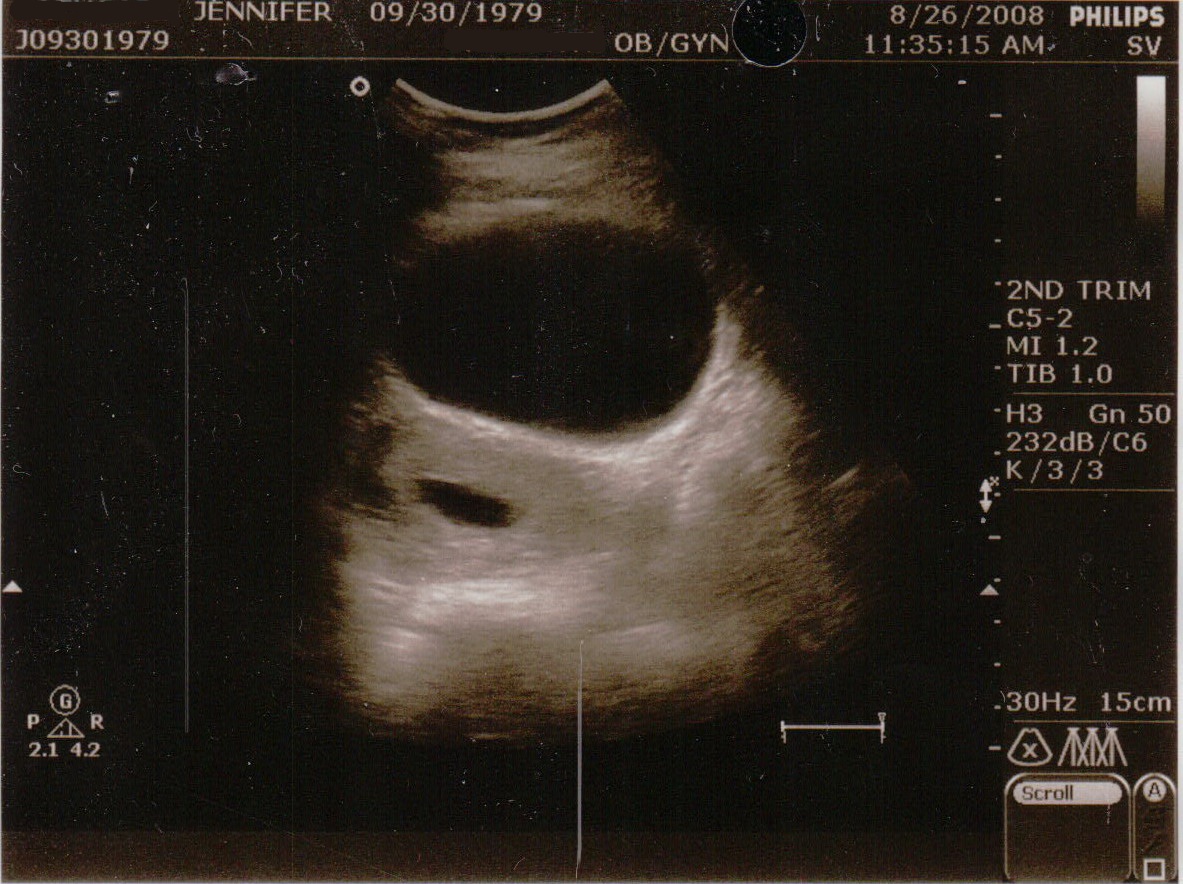

The first two images were during the regular abdominal ultrasound. The sac is the dark ovular hole on the left. The larger hole above it I believe is my bladder.

This image was during the transvaginal ultrasound, again the dark ovular hole in the center is the sac. I was supposed to be 11 weeks and 3 days along, but the sac was empty (blighted ovum 😦 ) and was measuring at only 6 weeks.